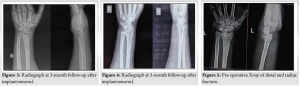

After the surgery, the wrist is placed in a splint or cast to prevent movement and support the initial healing process. Follow-up involves the use of sequential radiographs to evaluate the healing of the fracture and the correct positioning of any surgical implants. Dorsal distraction plating provides strong stabilization, allowing for prompt movement and restoration of function. Physical therapy is started once X-ray imaging confirms that the wrist has healed enough to regain its range of motion and strength. Subsequently, after the removal of the implant, adhesiolysis is carried out during the surgery to regain the mobility of the wrist joint. Dorsal distraction plating X-rays (Fig. 1, 2, 3, 4). ExFix X-rays (Fig. 5, 6, 7, 8, 9).

Although the initial radiological outcomes were similar in both groups, the ExFix group experienced a subsequent deterioration in alignment, leading to varied radiological outcomes as the study continued, particularly after 1.5 months. Nevertheless, this discrepancy did not reach statistical significance (P = 0.06).